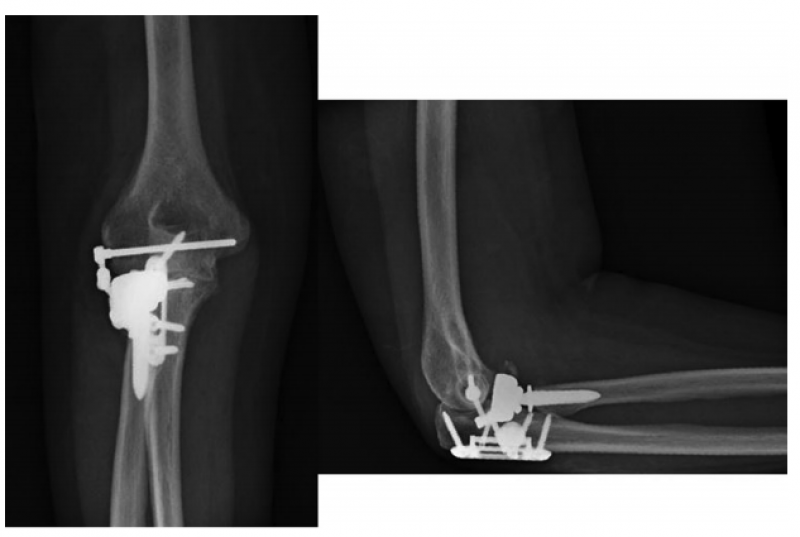

1、Lovy等采用鹰嘴雪橇板治疗Mayo II型鹰嘴骨折,在至少12个月的随访中,22例患者获得了满意的临床功能,均未取出内固定,也未出现感染或内固定相关的并发症,仅1例患者出现HO以及尺神经症状,做了关节镜下清理和尺神经前移。

7、Pasternack等提出了一种型的肘关节内固定架,只有10例患者(6例是三联征,2例新鲜肘关节脱位,1例陈旧肘关节脱位,1例外髁骨折),2016年获得FDA批准。平均术后74天后取出。内固定架能够减少外固定架带来的术后并发症,同时能够维持肘关节的稳定性,但由于初始损伤比较重,由于其他各种原因导致的二次手术率仍然较高。